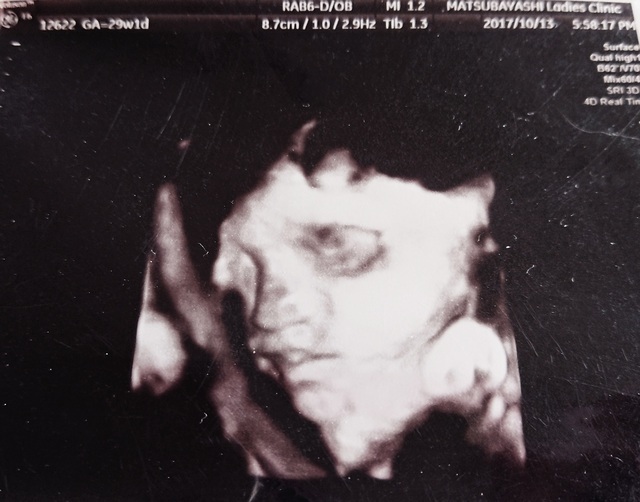

29週0日(29w0d・男の子)|yuiiing52 さん(31歳)

エコー写真撮影時のエピソード:

エコー写真はいつ見ても、どれが顔なのかどれが足とか全然分かりませんでした。3Dと4Dを同じに日に撮って、4Dの方が分かりにくくて、旦那様は全く分かってなくて、帰って録画したのを見て説明しました。

この3Dが1番きれいに撮れて、でも先生はボッコボコとエコーのやつでグイグイ押してたので、こんな押して大丈夫と不安でしたが、いい写真が撮れました。